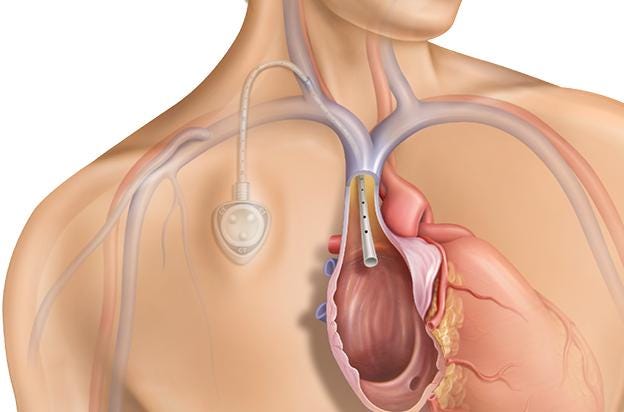

Bard PowerPort

The Bard PowerPort is an implanted catheter device used to deliver medications directly into the bloodstream, often for chemotherapy or long-term treatment. Lawsuits allege that the device can fracture or migrate, causing serious internal injuries, blood clots, infections, and the need for surgical removal. Manufactured by C. R. Bard, the product is the subject of a rapidly growing MDL. Plaintiffs claim the device was defectively designed and that safer alternatives were available. The litigation is currently in the coordinated discovery phase, with thousands of cases pending and expectations for future bellwether trials.